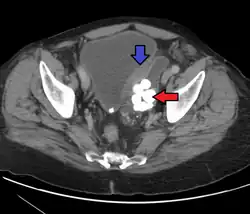

Transitional cell carcinomas are often multifocal, with 30–40% of patients having more than one tumor at diagnosis. The pattern of growth of transitional cell carcinomas can be papillary, sessile, or carcinoma in situ. The most common site of transitional cell carcinoma metastasis outside the pelvis is bone (35%); of these, 40 percent are in the spine.[10]